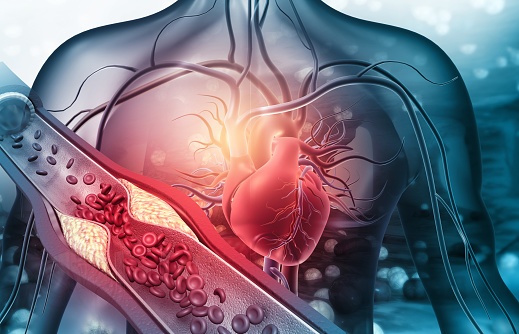

coronary artery disease

There is an urgent need to identify women at risk for cardiovascular disease to prevent adverse cardiac events. Yet, a ...

In patients with atrial fibrillation and coronary artery disease (CAD), researchers found that rivaroxaban monotherapy ...

In a recent study, published in BMC Cardiovascular Disorders, researchers evaluated the role of HOMER1, ...

In the BASKET-SMALL 2 randomized controlled trial, researchers compared the effect of a drug-coated balloon (DCB) ...

Peripheral artery disease (PAD) is a significant contributor in cardiovascular morbidity and mortality; However, ...

Researchers assessed the predictive value of post-systolic shortening (PSS) for early identification of myocardial ...

A pooled analysis of randomized trials found that moderate to severe coronary artery calcification (CAC) is associated ...

Coronary computed tomography angiography (CCTA) can detect atherosclerosis, even among individuals with no coronary ...

The results of a study show a link between the profile of serum fatty acids (FAs) and early-onset coronary artery ...